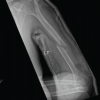

We present the case of a 16-year-old male who suffered a hypersupination injury while playing rugby. He attended his local orthopedic center where he reported pain and limited movement in his right wrist. On examination, he had swelling and diffuse tenderness of his right wrist, with restricted supination and pronation. Examination of his ipsilateral elbow and shoulder was normal and he was neurovascularly intact. Initial plain film radiographs of his right wrist showed a volar dislocation of the right distal radioulnar joint with associated ulnar styloid fracture (Fig. 1). CR was attempted at the time but failed (Fig. 2). He was then referred to our tertiary orthopedic unit.